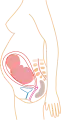

De acuerdo a su desarrollo, el embarazo se suele dividir en tres etapas de tres meses cada una, con el objetivo de simplificar la referencia a los diferentes estados de desarrollo del feto.

Durante el segundo trimestre (a partir de las 14 semanas de gestación) el desarrollo del feto puede empezar a ser monitorizado o diagnosticado.

Mes 2: Mide 3 cm y pesa 3 g. Desarrollo de brazos y piernas, así como del cerebro y órganos internos. Mes 3: Mide 10 cm y pesa 45 g. Desarrollo de los párpados y movimiento de las extremidades

Mes 3: Mide 10 cm y pesa 45 g. Desarrollo de los párpados y movimiento de las extremidades